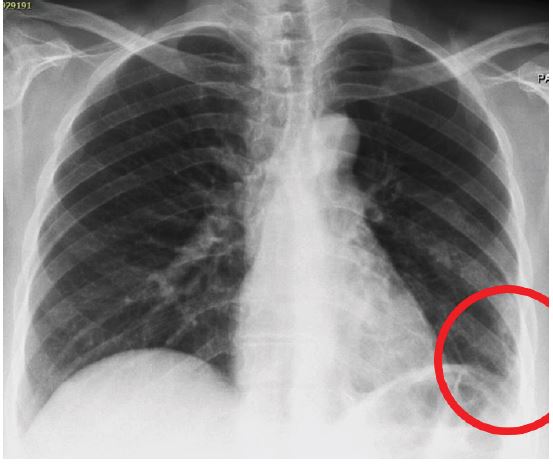

A 42-year-old male presented to our outpatient clinic with a 2-month history of persistent dry cough, mild exertional dyspnea, and occasional wheezing. He was a non-smoker with past history of Bronchial Asthma which was diagnosed 3 years back and patient was on Inhaled salbutamol on as needed basis. Clinical auscultation revealed a localized wheeze over the right lower lobe. Chest X-ray showed a suspicious opacity. CT chest revealed a well-defined lesion at the origin of the right lower lobe bronchus. Bronchoscopy visualized an endobronchial mass, and biopsy confirmed a typical carcinoid tumor.

Figure 1: Chest X-ray showing an opacity in the right lower lobe.